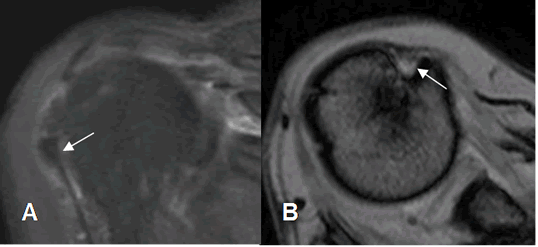

Fig 152. Tenosinovitis de la cabeza larga del bíceps.

A: RM axial en FFE y B: RM coronal en STIR. El tendón de la cabeza larga del biceps está rodeado por líquido, por tenosinovitis. En B hay adelgazamiento del tendón del supraespinoso y cambios inflamatorios, por ruptura parcial. (Flecha gruesa).